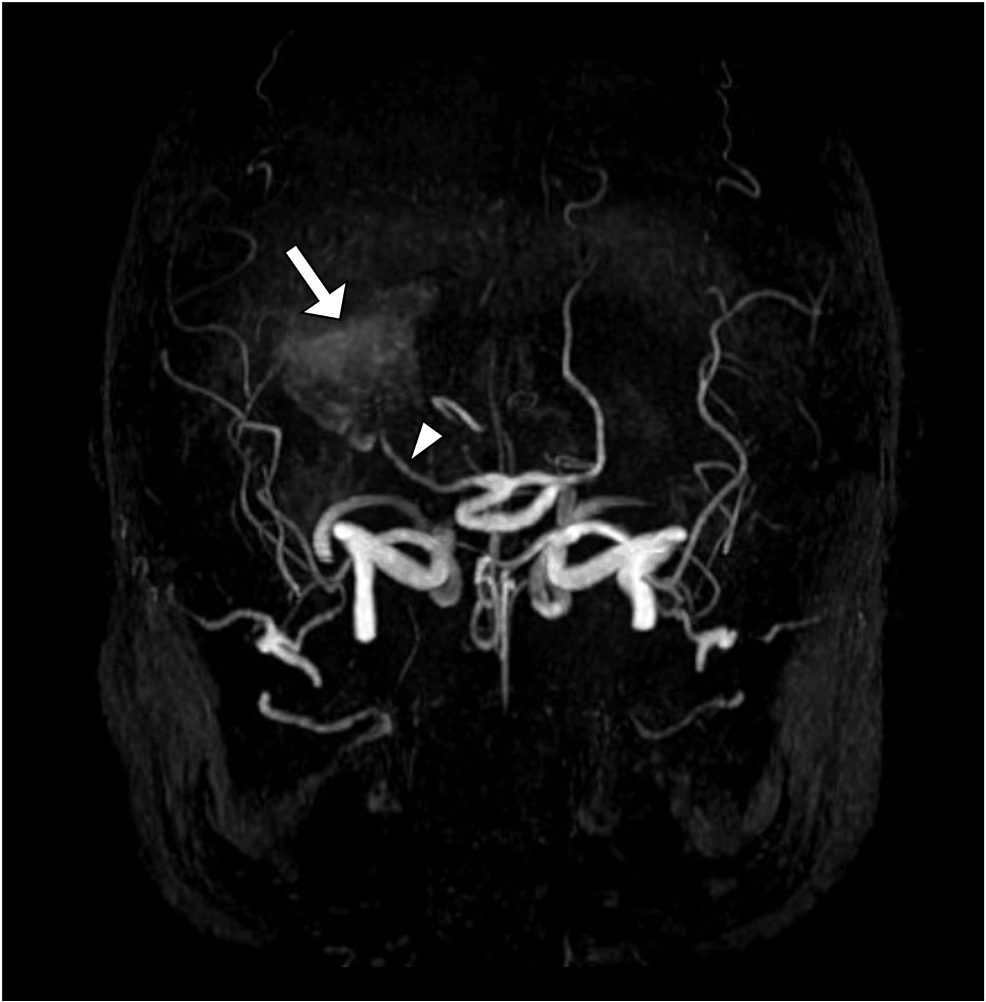

Los análisis de sangre no mostraron signos de infección o inflamación, lo que descartaba otras causas. El diagnóstico llegó con una resonancia magnética cerebral, que mostró una dilatación anormal y gigante en la arteria cerebral posterior derecha, confirmándose que se trataba de un aneurisma.

Los aneurismas en esta arteria en particular son bastante raros, siendo solo alrededor del 1% de todos los aneurismas intracraneales. Sin embargo, tienen una característica que los hace especialmente relevantes: tienden a ser de gran tamaño.

La arteria cerebral posterior es una carretera principal que suministra sangre a áreas vitales del cerebro responsables de la visión, como el lóbulo occipital. Cuando un aneurisma se forma y crece en esta zona, puede presionar las estructuras circundantes, lo que explica por qué este paciente sufría de alteraciones visuales tan específicas.